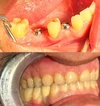

علاج الزرعات السنية